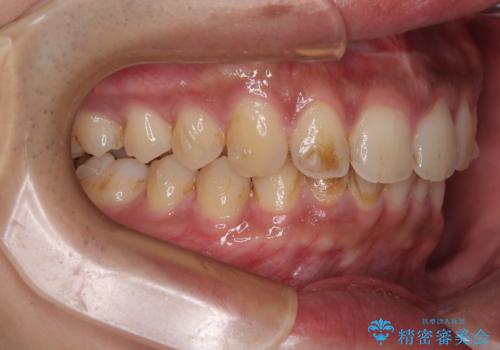

- 上の前歯の正中離開(すきっ歯)と、下顎前歯部の叢生(デコボコ)を主訴に来院された患者様の症例です。

「目立ちにくい装置で治療したい」とのご希望があり、透明のマウスピース矯正であるインビザラインを用いて矯正治療を行いました。